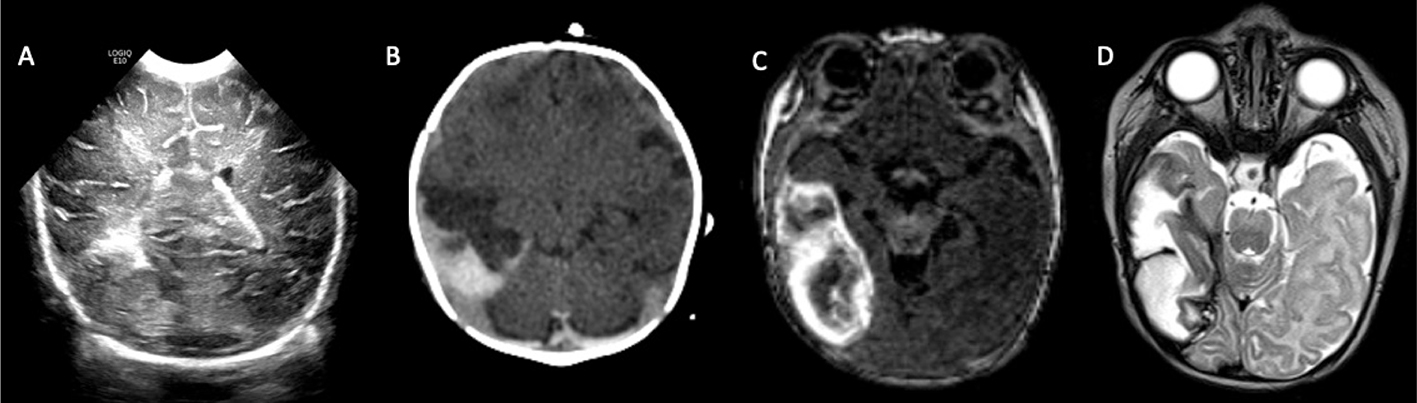

The incidence of perinatal hemorrhagic stroke is approximately 1 in 6000–9000 live births (6871). Compared with PIS, fairly little is understood about its risk factors, etiologies, and outcomes. While intraventricular hemorrhage in premature neonates originates from a fragile germinal matrix, the mechanisms responsible for late preterm and term hemorrhagic strokes remain unclear, and the majority are described as idiopathic (69, 70). In term infants, isolated intraventricular hemorrhage is less common than intraparenchymal hemorrhage and, if present, may be the result of CSVT (7274). Causes of hemorrhagic stroke include congenital and acquired coagulopathy, CSVT (particularly cerebral medullary veins thrombosis), vascular malformations, and hemorrhagic conversion of ischemic infarct (arterial or venous) (69). Hemorrhagic disease of the newborn is more prevalent in infants who have not received vitamin K at birth and in infants of mothers taking blood thinning medications, such as warfarin, phenytoin, or barbiturates, during pregnancy (75, 76). Acquired coagulopathies include neonatal alloimmune thrombocytopenia or disseminated intravascular coagulation. Some genetic arteriopathies associated with both fetal and neonatal hemorrhagic stroke include collagen IVA and JAM3 mutations, which can appear identical to hemorrhagic venous infarctions (7784). In addition to hemorrhages occurring later in life, fetal and neonatal patients may present with subpial hemorrhages (Figure 8), which may be related to local venous thrombosis or birth trauma (8587). In these cases, blood is seen between the pia mater and the displaced brain parenchyma, often accompanied by venous infarction and subarachnoid or parenchymal blood.

Fig 8

Figure 8. Subpial hemorrhage. A 17-day-old female with hypoplastic left heart syndrome status post Stage I Norwood with BT shunt. Coronal sonographic images (A) shows a heterogeneous lesion in the right temporal lobe. Axial non-contrast CT (B) shows the lesion to be a mixed intensity peripheral lesion in the right temporal lobe. T1- (C) and T2-weighted (D) images demonstrate a subpial hematoma in the right temporal lobe.